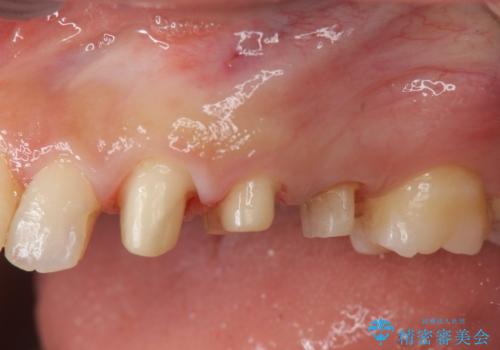

- 歯ぐきの腫れや、歯の内部が黒く見えることからの虫歯の治療を求めて来院されました。

虫歯が大きかったことから、神経の温存はできたものの歯ぐきよりも深い虫歯の問題を解決するため部分矯正治療を併用したセラミック治療を行うこととしました。